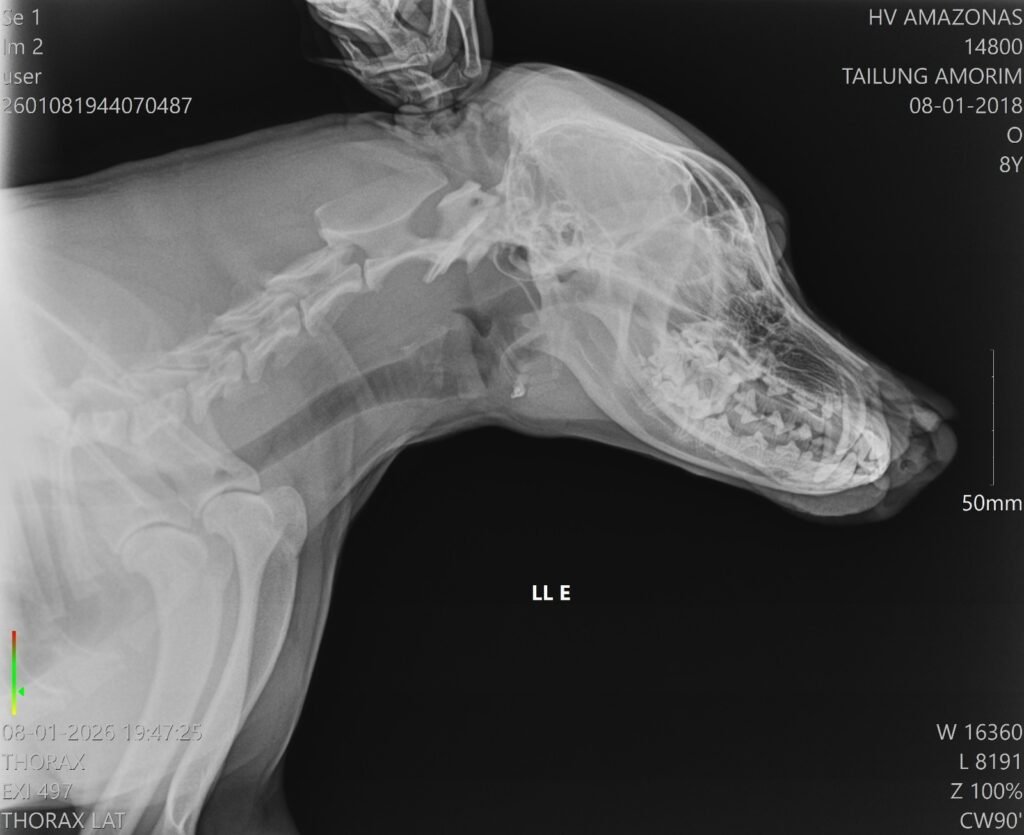

De acordo com a equipe hospitalar, o cachorro apresentava uma lesão profunda na região do focinho, mas estava consciente e respondeu bem ao atendimento. A cirurgia foi bem-sucedida e o animal já foi encaminhado para casa, onde permanecerá em observação pelo tutor, além de seguir acompanhado pela equipe multidisciplinar do HPVet-AM.